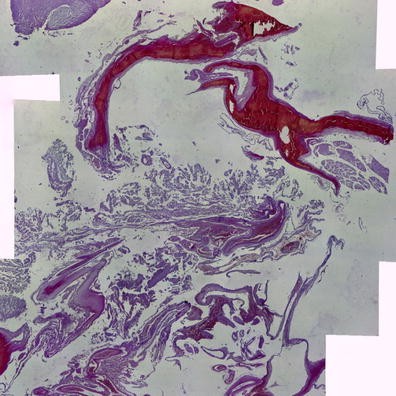

Method: A total of 15 patients with SDHB-mutation were analyzed genomic DNA, clinical data on family history, catecholamine types, tumor metastasis, patient prognosis, and histology of the tumors. Histologic analyses were performed using the new classification named Grading of adrenal pheochromocytoma and paraganglioma (GAPP) classification that was made based on a nationwide Japanese survey. All tumors were scored from 0 to 10 points, and were also graded according to three differentiation types depending on the total score: well (0–2 points), moderate (3–6) and poor (7–10).